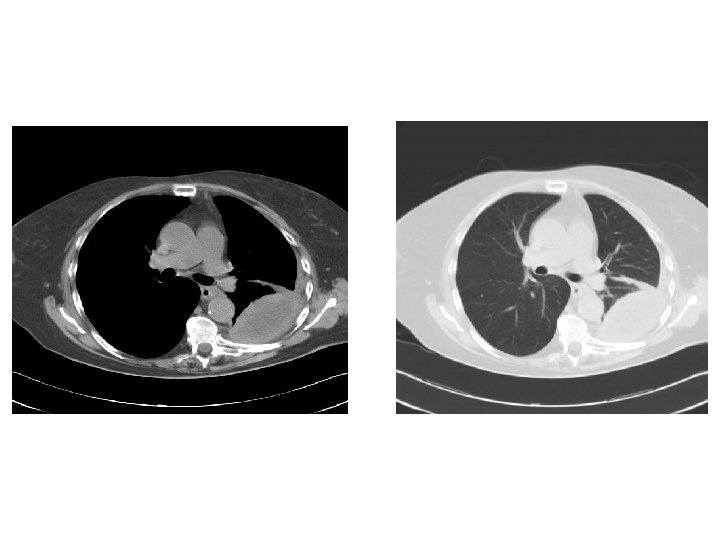

Cas clinique 1 • • Homme 65 ans suivi pour BPCO Retraité SNCF Tabagique Asymptomatique hormis BPCO

Cas clinique n° 2

• Quelques mois plus tard : AEG, douleur basithotacique droite, dyspnée • Épanchement pleural droit 3/4 de l’hémichamp

Que faites-vous? • Ponction pleurale exploratrice : – Biochimie (ac hyaluronique) – Cytologie/ana-path • Biopsie pleurale? • Thoracoscopie – Diagnostic – « Traitement »

Cas clinique

Quel diagnostic suspectez vous? Mésothéliome